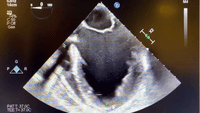

This is the ME 4 chamber for a patient with non-ischemic CM, coming for Heartmate 3 LVAD...

...And this is the identical picture post-bypass, with the VAD now set to 5300RPM.

Anyone want to venture a guess as to what that thing is that we’re now seeing in the left atrium? Are we worried? Is there anything we could do to fix it?

@nimbus and @1halfMVsquared nailed it: this is left atrial appendage inversion. We dropped the VAD speed and increased afterload to increase LA pressure, and it spontaneously reverted. I’ve seen this a few times now, but never (yet) seen it cause mitral inflow obstruction